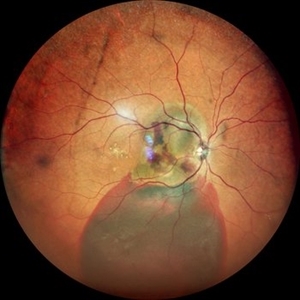

Idiopathic Polypoidal Choroidal Vasculopathy Idiopathic Polypoidal Choroidal VasculopathyMay 11 2022 by Pramod Kumar Suman, MBBS, MD Fundus photograph of an 59-year-old male with clinically visible orange-red sub-retinal nodules with sub-retinal hemorrhage. Photographer: Pramod Kumar Suman, Retina Foundation, Ahmedabad Condition/keywords: polypoidal choroidal vasculopathy (PCV)